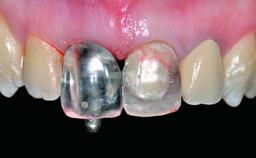

Replacement of a Failing Restored Upper Right Central Incisor, Ridge Preservation and Early Placement of an RC Bone Level Implant

A 23-year-old female, healthy and non-smoking patient had had tooth 11 temporarily restored following a trauma in adolescence. As the patient’s growth had since come to an end and the crown had fractured, she requested an implant-supported restoration of tooth 11. Moreover, the contralateral tooth 21 presented an old composite restoration at the mesial incisal edge. The periodontal tissues were healthy with periodontal probing depth values below 3 mm, but some inflammation was observed around the semi-submerged root of tooth 11.

Retention Cemented, with prosthesis margin < 3mm submucosal Cemented, with prosthesis margin < 3mm submucosal

Provisional Implant-Supported Prosthesis Prosthodontic margin > 3 mm apical to mucosal margin Prosthodontic margin > 3 mm apical to mucosal margin